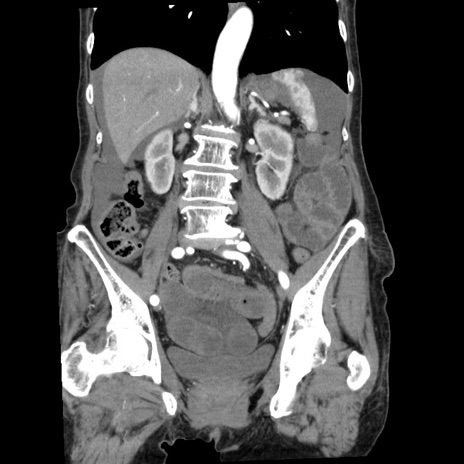

症例1(冠状断像)

【症例】80歳代女性

【主訴】腹痛

【現病歴】8時間前から腹痛あり来院。

【既往歴】糖尿病、脂質異常症、子宮体癌にて子宮全摘術

【身体所見】意識清明・会話良好だが腹痛で苦悶様、全腹部にわたって反跳痛と圧痛あり

【データ】WBC 13600、CRP 0.14、LDH 224、CK 90